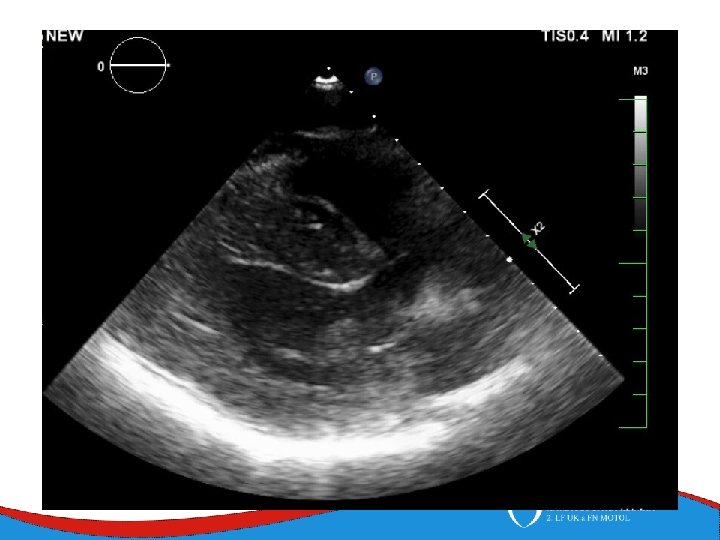

Dilated cardiomyopathy Dilated left ventricle with systolic dysfunction in the absence of coronary ischemia or loading conditions capable of causing such dysfunction (CAD, hypertension, valvular disease, congenital heart disease). Prevalence 1/2 500

Patology and patophysiology Myocytal malfunction (atrophy/hypertrophy) Instersticial fibrosis → impaired systolic and diastolic function → compensatory mechanisms Dilatation (escpecially LV) - diffuse, RV (x CAD) Low CO, congestion Mitral regurgitation, secondary

Signs, symptoms and diagnostics • Heart failure- low CO, congestion • Arrhythmias • Sudden death • SVT, AF- mitral regurgitation- atrial dilatation • Thrombi in left ventricle/ left atrial appendage – CMP • ECG • ECHO – ventricular dilatation and dysfunction • Lab – NT-pro. BNP • Selective coronarography- CAD exclusion • Stress test- prognosis • MRI • EMB– inflammatory CMP